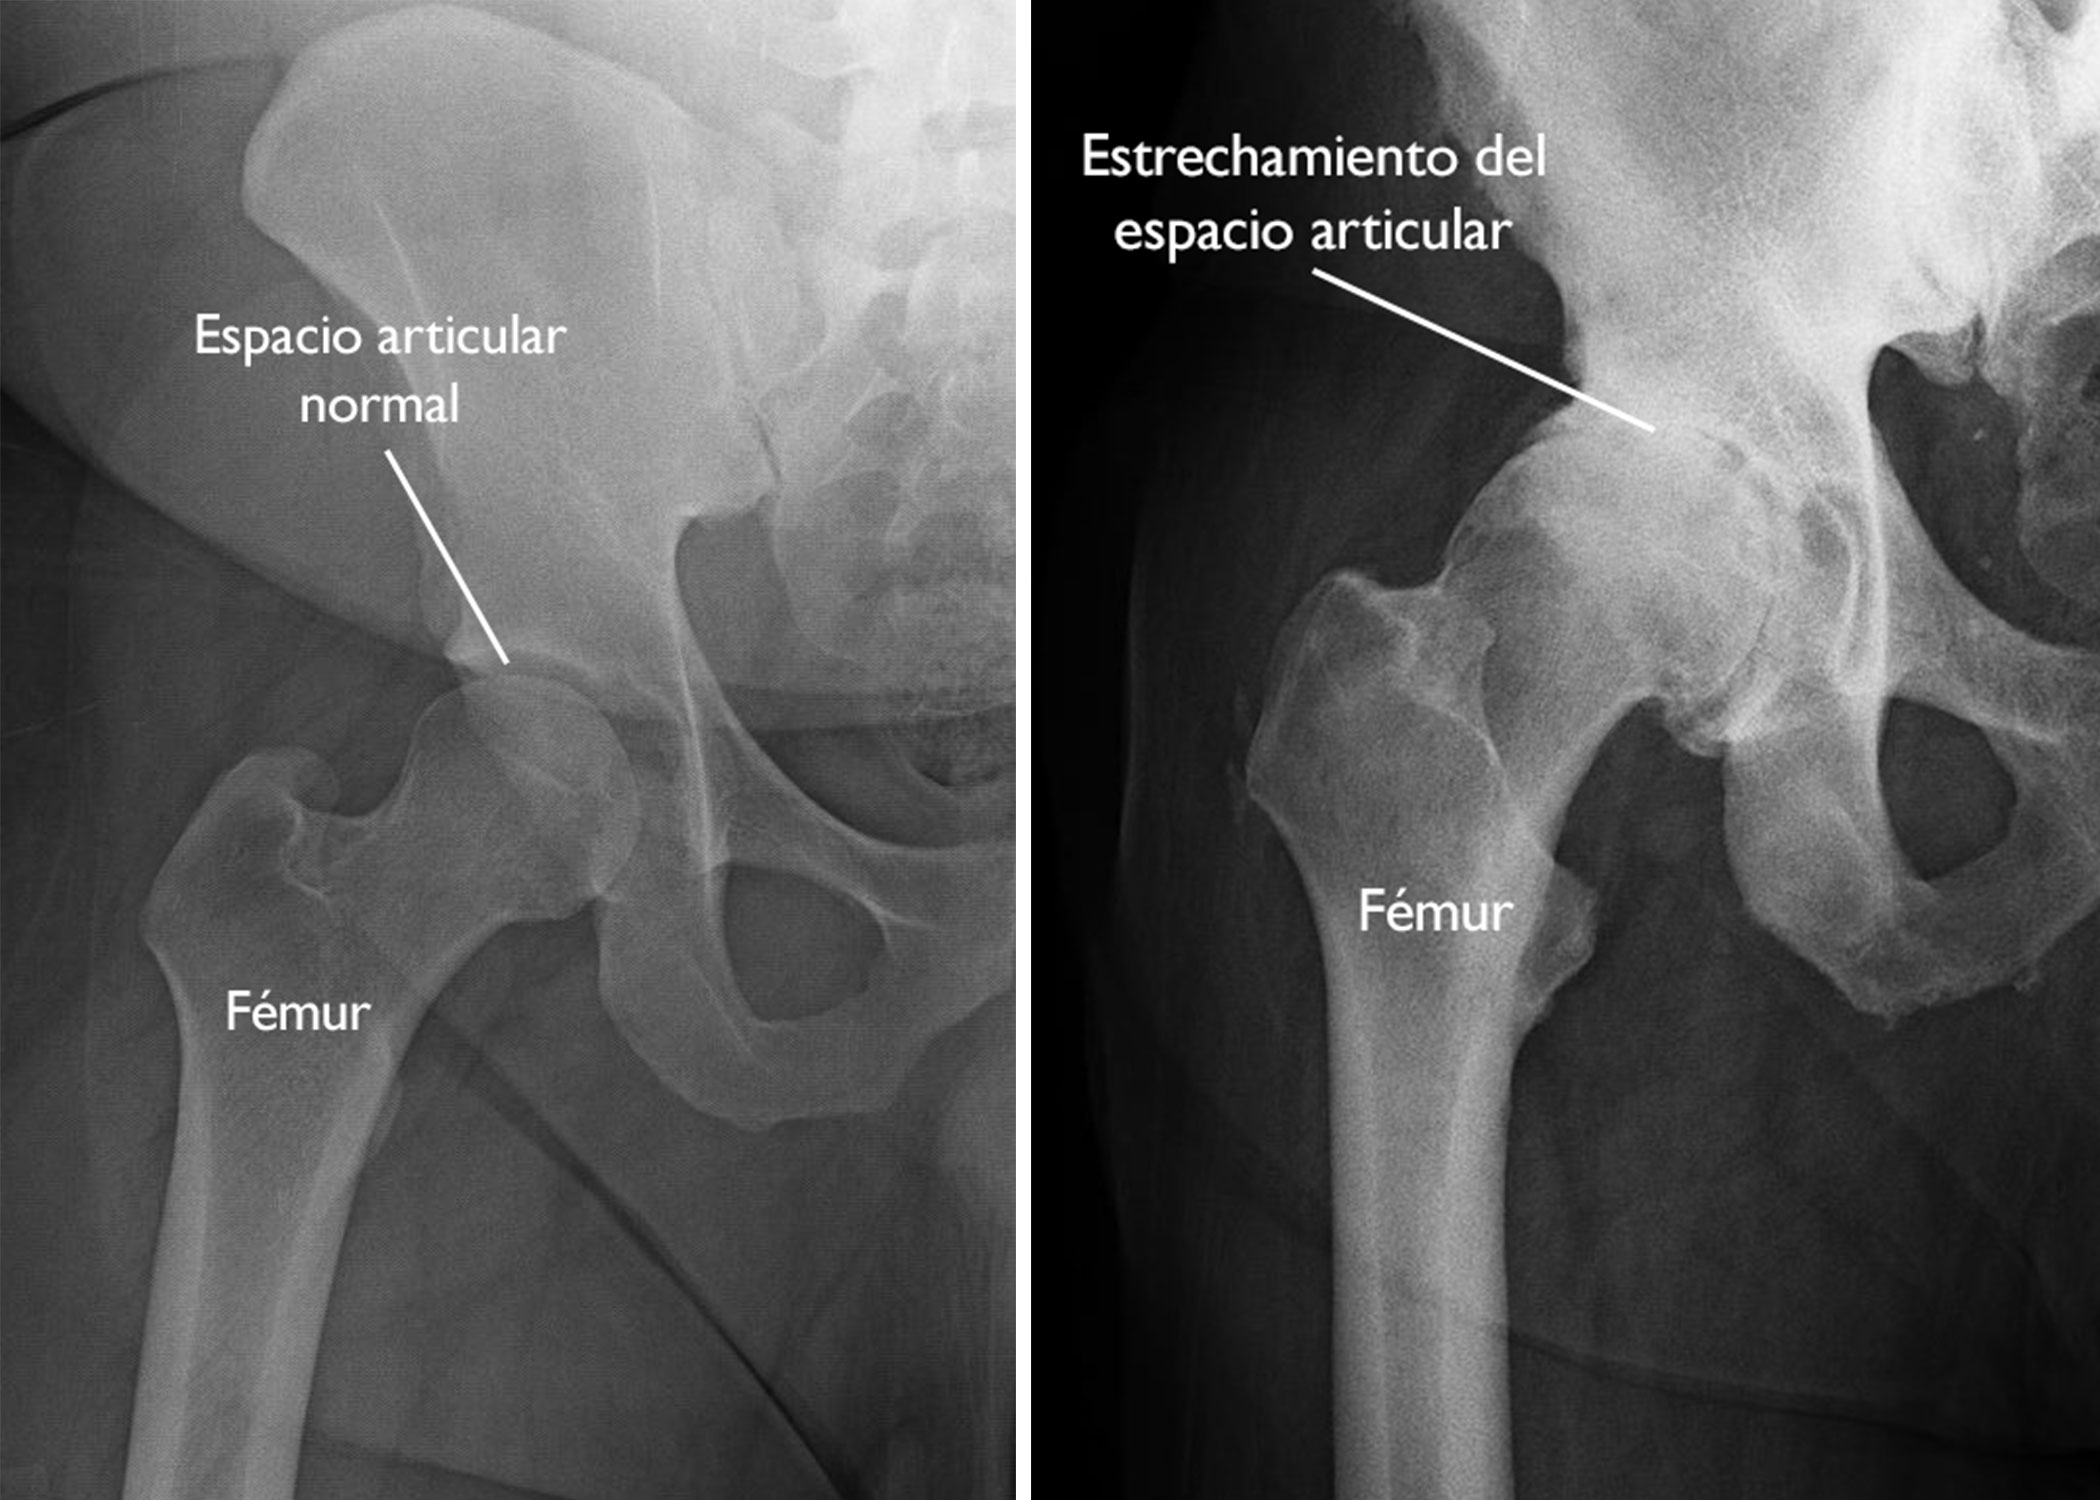

• Radiografía: Estrechamiento articular, osteofitos y esclerosis.

Radiografia de artrosis de cadera